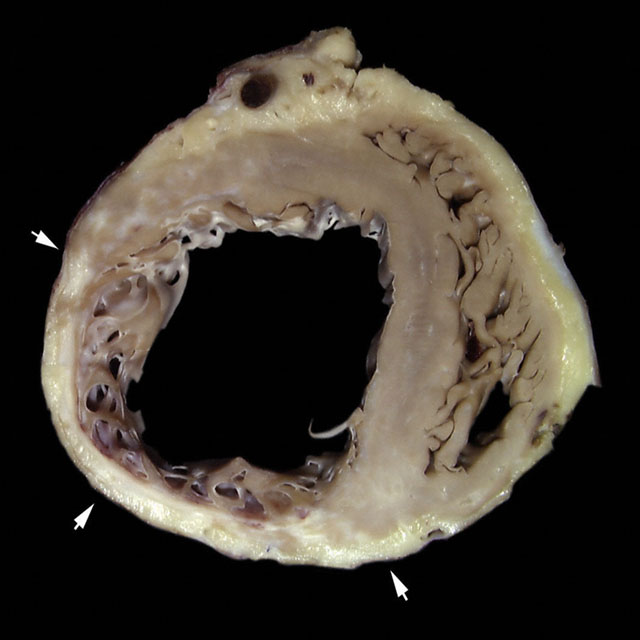

Myocardial Infarct - Healed Transmural - I

Gross image of a well healed posterolateral transmural infarction. The arrows show the infarct and its lateral and posterior limits. The healed area shows a thinned wall with loss of all the compact zone of the myocardium (transmural infarction).

Only some of the trabecular myocardium seems viable. The anterior and septal borders of the infarction show white scar tissue representing replacement fibrosis.